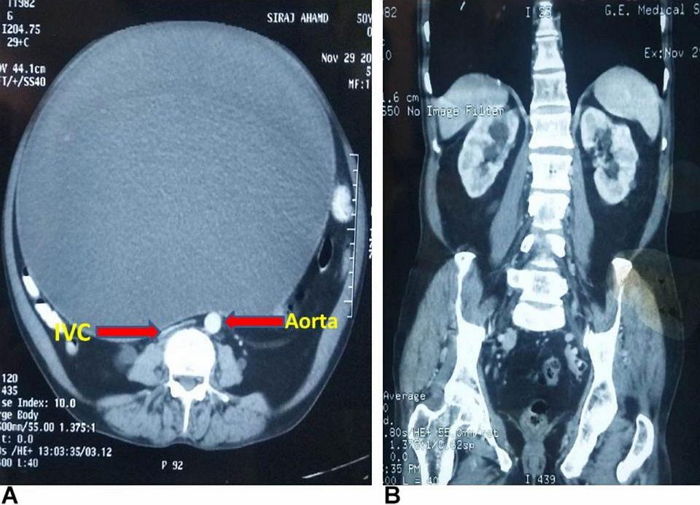

検査の結果、男性の体の中には長い時間に排出されなかった尿がいっぱい溜まってありました。

X-ray撮影画像で鮮明に見える男性の膀胱は、一般の人々よりも6倍以上に膨張した状態でした。

男性の深刻な状態に驚いた医師は直ちに尿を抜くための施術を行い、4時間をかけて、体から尿をスッキリと除去しました。

男性の体から排出された尿の量はなんと11リットルでした。これは、膀胱の通常の容量である400〜600mlの18倍を超える量でした。

男性を診断した医師は、「最初にX-ray写真を見た時は膀胱の大きさに目を疑った」と当時の状況を伝えました。